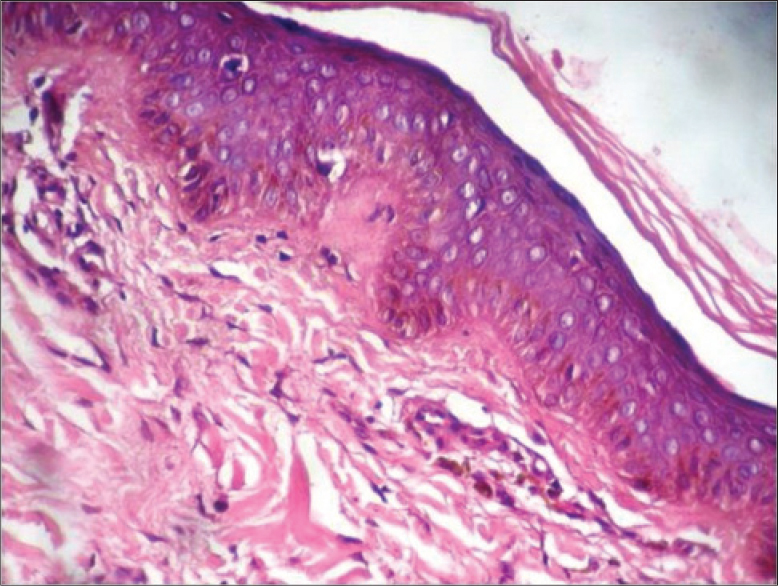

Penile melanosis, also referred to as penile lentigines or penile freckling, is characterized by the presence of dark spots or patches on the skin of the penis. These spots can vary in size and number and can appear anywhere on the penis, from the head (glans) to the shaft. The condition arises from an accumulation of melanocytes, the cells responsible for producing melanin, the pigment that gives skin its color. These melanocytes clump together, leading to the formation of dark brown or black dots.

While generally harmless, it's understandable why individuals might seek more information. Although genital melanosis is considered benign, some research has indicated a potential link between genital melanosis and malignant melanoma. One study reported that melanosis was the most common pigmented lesion in the genital region, and that the glans penis was the most frequent location for pigmented lesions in males [4]. Therefore, understanding the subtle differences and knowing when to seek professional medical advice is critical.

Treatment options for penile melanosis include laser therapy or surgical removal. Dermoscopic findings revealed a fibrillar pattern, indicating a potential diagnosis of penile melanosis. Histopathological analysis of a skin biopsy specimen confirmed keratinocyte hyperpigmentation and ruled out any melanocytic abnormalities or proliferation, supporting the diagnosis of penile melanosis.

Penile melanosis is an accumulation of melanocytes in the skin of the penis. These cells clump together in a single space and cause melanosis spots, which are dark brown or black dots. It is unknown why melanocytes accumulate this way, and the exact causes of penile melanosis are unknown.